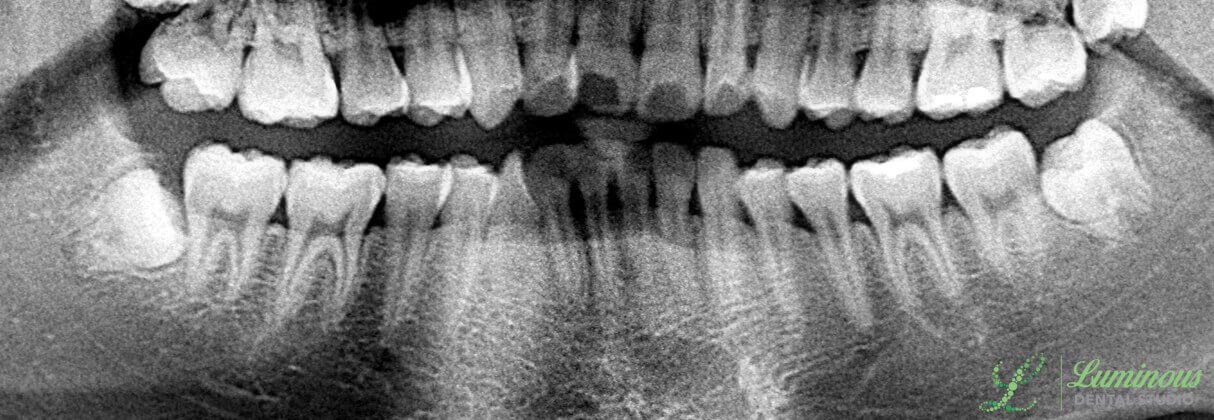

Impacted third molars extracted in Frisco, TX by Minho Chang DMD.